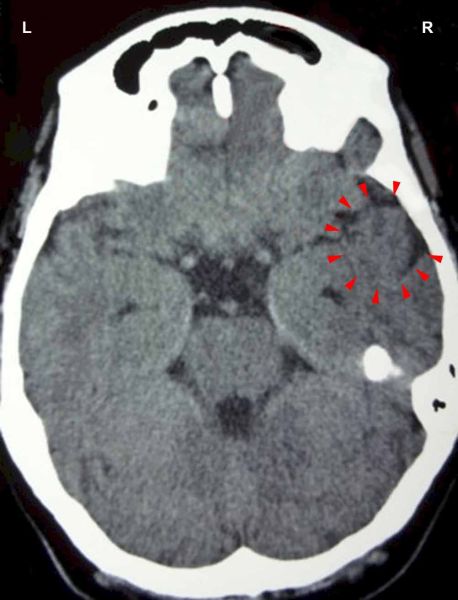

On this CT scan we see the impact of a stink conflict in the area of the sensory cortex that controls the nasal mucosa of the left half of the nasal cavity (view the GNM diagram). For a right-handed person the conflict is associated with his/her mother or child; for a left-hander with a partner. The uneven, partly edematous ring of the Hamer Focus reveals that the person has already resolved the conflict and is now in the healing phase with symptoms of a cold.

This CT scan presents a Hamer Focus in PCL-A with fluid accumulation (brain edema) in the control center of the olfactory nerves (red arrows - view the GNM diagram), indicating that the related conflict has been resolved. With water retention due to an active abandonment or existence conflict involving the kidney collecting tubules (yellow arrow), the brain edema increases significantly.